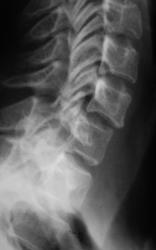

Пациент предъявляет жалобы на боли в плечевом суставе. Направлен на рентгенографию плечевого сустава хирургом. Со стороны плечевого сустава (рентгенограмма) патологических изменений не выявлено. Произведено исследование шейного отдела позвоночника.

Валентин Львович! Не могу посчитать позвонки, перекрываются углом нижней челюсти. Ну то, что имеется остеохондроз, это понятно. Аномалия развития в виде расщепления остистого отростка позвонка или C2 или C3 позвонка. Но откуда у С1 остистый отросток?

Что же касается данной шеи: считаю необходимым дообследования - рентгенография С1 позвонка "через рот", более информативно будет.